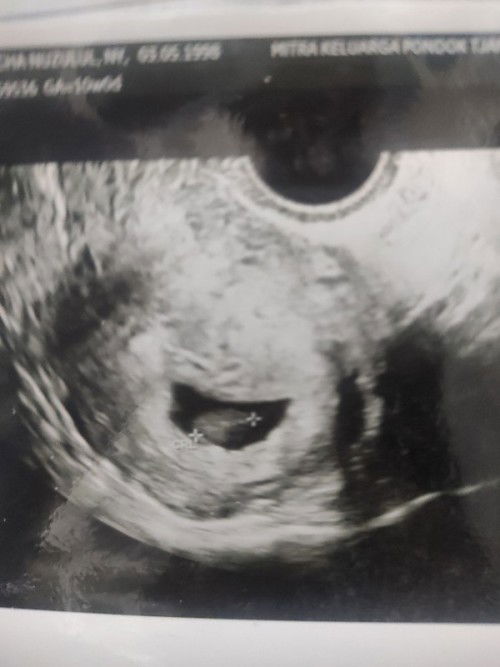

Kantung tidak beraturan djj negatif 8 w

Bunda saya mau cerita, hari ini saya usg uk 8 mg dinyatakan dokter janin saya tidak ada djj dan kantong ireguler alias tidak teratur. diagnosa dokter uda kematian mudigah. Tp disuruh kontrol 1 mg untuk cek lg kalau gaada djj harus kuret. saya memang tidak ada gejala mual muntah, sblmnya siklus haid tidak teratur, dan dokter juga menyatakan saya pcos jadinya mempertahankan janin di tm 1 itu susah ada ga disini bunda yg kasus nya mirip kayak saya tp janin bisa sehat, atau memang sesuai dg prediksi dokter harus kuret. #seriusnanya